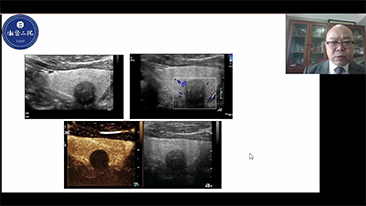

??? ?? ??? ?? ???? ? ??? ?? ??? ?? ??? ??? ??? ???. ???? ??? UWN+ ?? ?? ??? ?? MI??? ??? ??? ?? ?? ??? ?? ?? ?? ???, ?? ?? ?? ???? ??? ? ????.